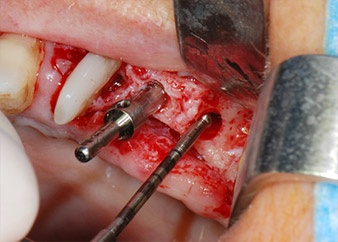

Les lits implantaires ont été préparés sur les sites 25 et 26 à l'aide d'instruments rotatifs, utilisés dans un contre-angle avec un rapport de transmission 20:1 avec un nouveau moteur d'implantologie puissant (Implantmed, W&H) (Fig. 8).

moteur d'implantologie

Fig. 8 : Préparation par rotation du lit implantaire avant le plancher du sinus maxillaire en position 25, effectuée à l'aide d'un nouveau moteur d'implantologie.